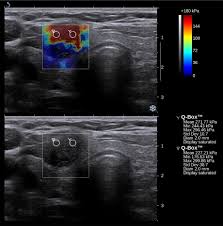

Die Ursache kann ein Adenom sein. Warme Knoten sind aktiver als normales Schilddrüsengewebe und produzieren demnach auch mehr Hormone. Heiße und kalte Knoten Kalte Knoten werden im Szintigramm blau oder violett angezeigt und sind Schilddrüsenbereiche die nur noch wenige bis gar keine Hormone mehr bilden.